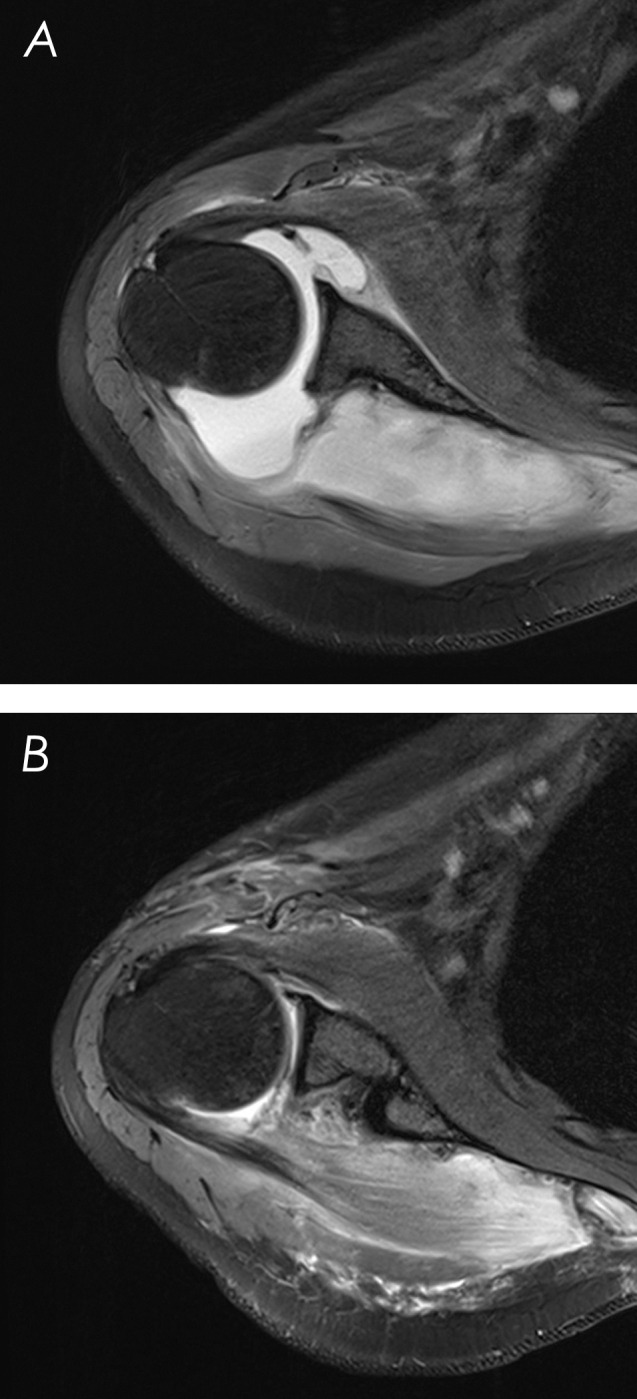

我们报告了一位31岁的免疫功能低下的女性,患有肩关节脓毒性关节炎和冈下脓肿,在关节内注射后出现继发于腋窝神经病变的瘫痪。12个月时,活动能力和正常功能恢复。这是首次报道的成人病例,强调免疫功能低下患者需要高度怀疑脓毒性关节炎,并强调有效的管理策略。

We present a 31-year-old immunocompromised woman with shoulder septic arthritis and an infraspinatus abscess presenting with paralysis secondary to axillary neuropathy after an intra-articular injection. At 12 months, mobility and normal functioning were restored. This first reported adult case highlights the need for high suspicion of septic arthritis in immunocompromised patients and emphasizes effective management strategies.